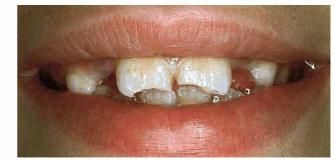

Figur 323s1823d e 18-8A: This 6-year-old girl fractured her maxillary central incisors in an accident.

Figur 323s1823d e 18-8B and C: The two central incisors were beveled and bonded with composite resin.

Figur 323s1823d e 18-8D and E: Ten years later, the patient still retains her original bonding, although reveneering has been done to maintain appearance